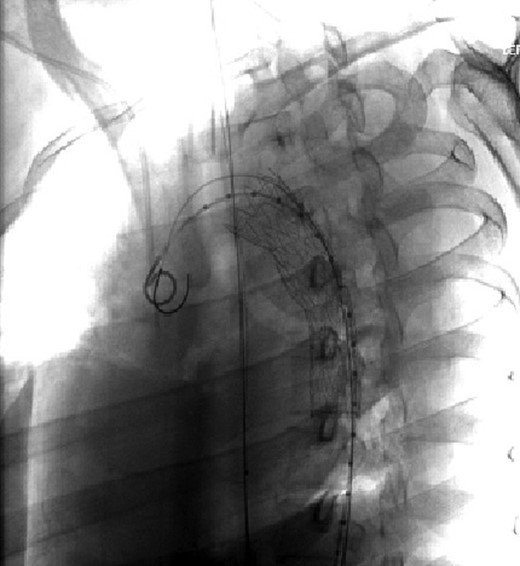

Chest, pelvis and right lower extremity X-rays were obtained. Chest X-ray findings are shown in Fig. 1. Pelvic X-ray was negative for acute injuries. Right lower extremity X-ray revealed the presence of a right tibia-fibula fracture and the right lower extremity was immobilized with a posterior splint.

Aortic arch and descending thoracic aorta visualized by CTA with contrast pre-placement of stent.